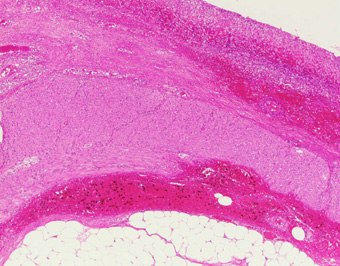

| 壊死部の固有筋層外縦層が萎縮し消失している.(HE,×4) |